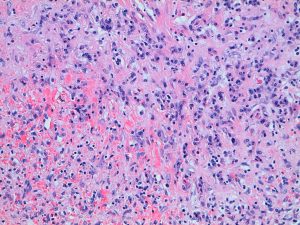

El informe histopatológico fue: macroscópicamente se aprecia parénquima esplénico de arquitectura alterada por la presencia de una lesión sólida, de contorno polilobulado e irregular; presenta áreas de aspecto hemorrágico y una zona central de aspecto cicatricial, blanquecina y la consistencia al corte era firme y elástica (ver Figura 2). Desde el punto de vista microscópico, la lesión corresponde a una proliferación de pequeños vasos con expresión inmunohistoquímica para CD34 y CD31 en un estroma densamente fibroso, con un contorno lobulado irregular, no encapsulado pero expansivo, que no contacta con los márgenes de resección (ver Figura 3). En conclusión: pieza de esplenectomía con lesión de transformación nodular angiomatosa esclerosante.

Figura 3. Aspecto microscópico: nódulos compuestos por una proliferación de estructuras vasculares con infiltrado inflamatorio de tipo mixto.

Desde el punto de vista histopatológico, la SANT muestra Infiltrados linfoplasmocitarios, estroma fibromixoide y nódulos angiomatoides en la pulpa roja esplénica. El estudio inmunohistoquímico de estos nódulos muestra 3 tipos de estructuras vasculares: capilares (CD34+/CD31+/CD8−), vénulas (CD34−/CD31+/CD8−) y sinusoides (CD34−/CD31+/CD8+) (13).